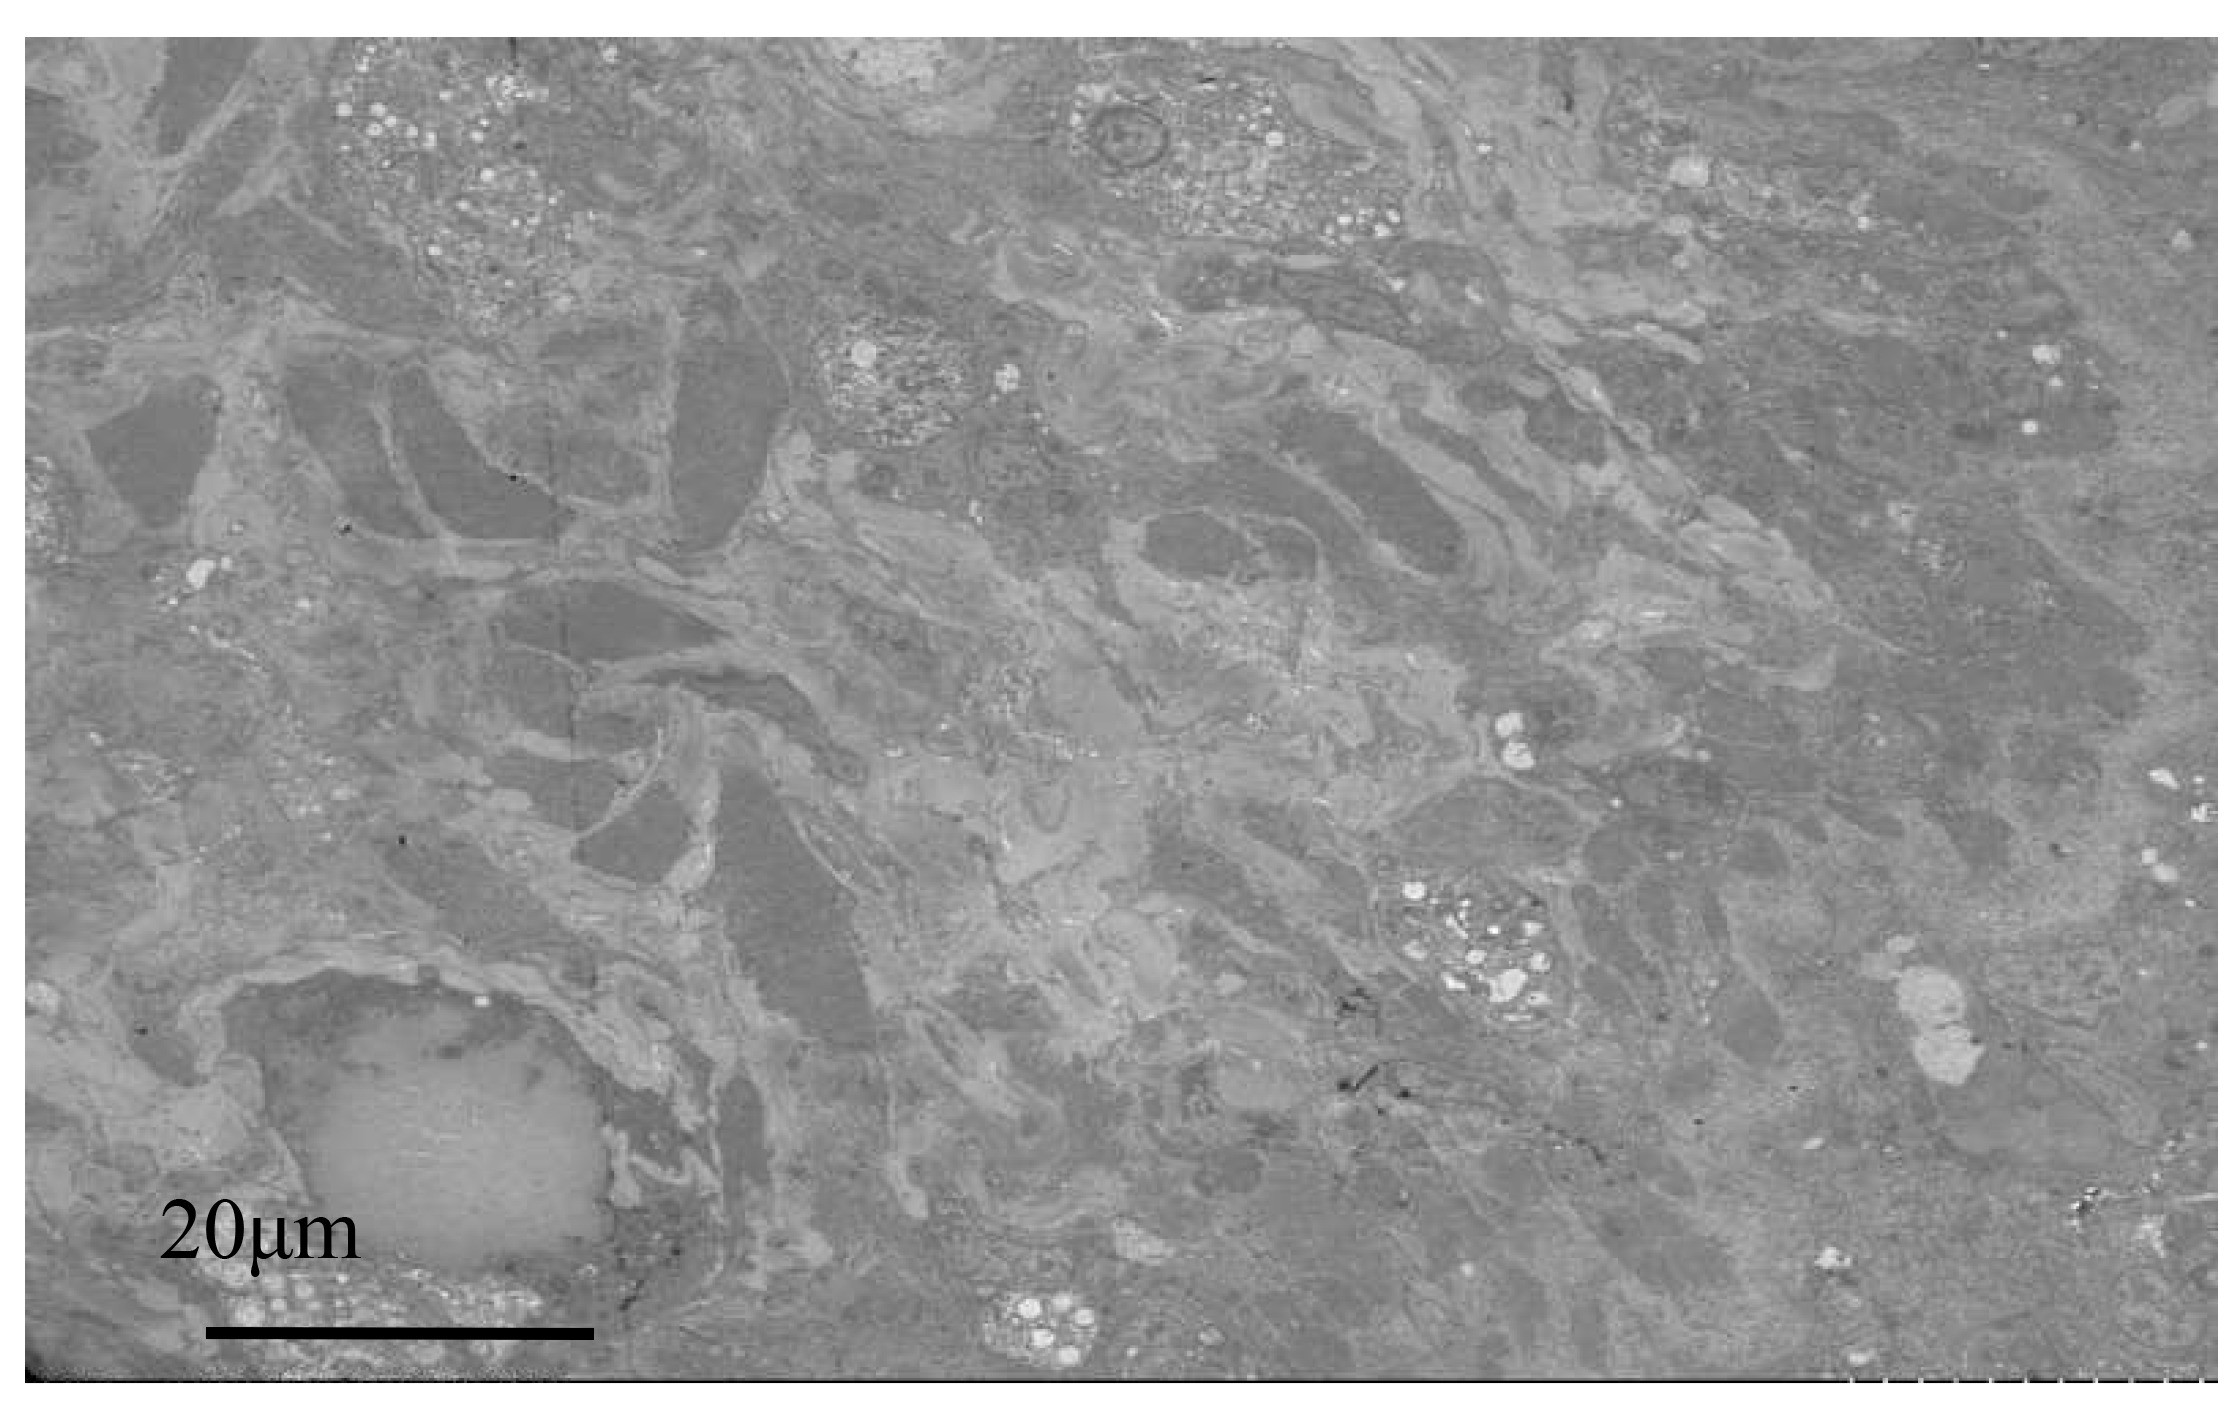

Electron microscopy images of healthy oysters showed that the epithelial layer of the mantle contained a large number of A-type columnar epidermal cells (Fig. 5A), some arranged in a monolayer and some scattered throughout the layer. The cells were about 7 to 14 μm in length, with a nucleus that occupied most of the cell. The nuclei of A-type columnar epidermal cells had relatively distinct euchromatin and heterochromatin, which were mostly located in the middle and lower parts of the cells. The organelles were relatively intact. After infection by Polydora (Fig. 5B), the overall image of the oyster mantle appeared darker than that of healthy individuals, with a particularly prominent staining of the epithelial layer area. This was due to the abnormal increase of secretion granules and pigment particles in the epithelial layer caused by the Polydora infection. The HE staining also confirmed this, as the pigment particles and secretion granules in the epithelial layer area of the marginal membrane protrusion of the infected individual were significantly increased, and the internal connective tissue area was significantly darker than that of healthy individuals.

Below the basement membrane, there was some disordered white zona pellucida (Fig. 6), consisting of electron-transparent granulocytes and secretory cells, that flooded between the epithelium and connective tissue layers. The overall structure inside the marginal membrane of healthy oysters was clear, with a normal nucleus morphology, complete nuclear membrane, and no chromatin shrinkage or vacuolization inside the nucleus. The outer mitochondrial membrane was clear, and the inner crest was relatively clear. Lysosomes were small, with a clear outer membrane and homogeneous internal substance, and the endoplasmic reticulum was laminated and relatively normal (Fig. 7A). In infected individuals, cells showed obvious pathological changes, with small fractures in the nuclear membrane, chromatin shrinkage, and vacuolization in the nucleus. A large part of lysosomes, the Golgi apparatus, endoplasmic reticulum, and mitochondria had dissolved and disappeared, and the only remaining morphological structure of the endoplasmic reticulum and cellular mitochondria was not obvious, showing semi-degenerate and dissolved forms. The cytoplasm also appeared lysed and there was severe vacuolization (Fig. 7B).